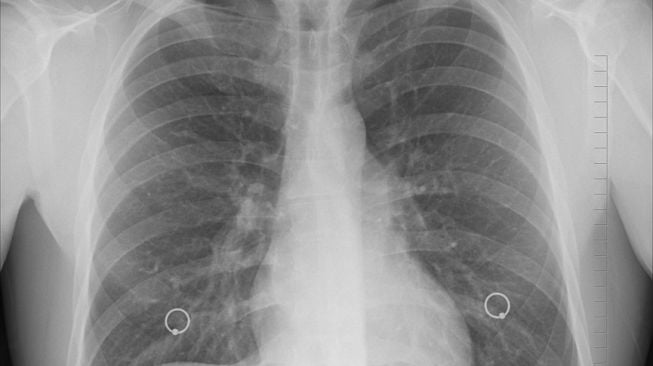

Heboh Pneumonia di dalam China kemudian Eropa, Kemenkes: Penyebarannya Tidak Secepat Virus penyebaran virus Corona

Organisasi Aspek Kesehatan Bumi atau WHO melaporkan adanya peningkatan perkara pneumonia yang digunakan mayoritas menyerang…

Apa Itu Mycoplasma Pneumoniae? Penyebab Lonjakan Wabah Misterius pada China

Penemuan bakteri bernama Mycoplasma pneumoniae belakangan ini berada dalam menjadi perbincangan rakyat lantaran diduga jadi…

Dokter RSCM: Infeksi Pneumonia Mycoplasma Lebih Ringan Daripada penyebaran virus Corona

Komunitas diminta tidak ada perlu khawatir dengan adanya ancaman infeksi pneumonia mycoplasma yang tersebut berisiko…

6 Kasus Pneumonia Mycoplasma Ada di tempat RI, Kemenkes Tidak Tutup Kemungkin Adanya Pandemi Baru

Kementerian Aspek Kesehatan tiada menangguhkan kemungkinan terjadinya pandemi baru setelahnya adanya laporan wabah pneumonia mycoplasma…